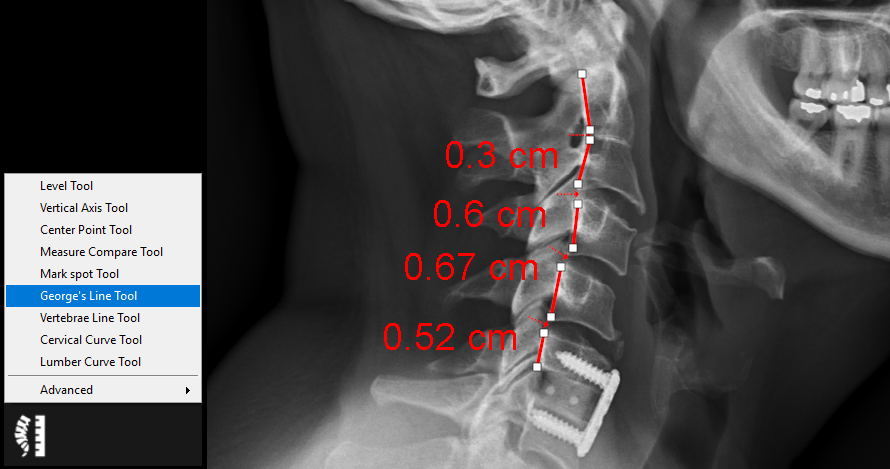

9.5.6. George’s Line Tool

The George’s line tool is used to measure the intervertebral disc space. Follow the instructions below to use this tool:

1.      Select the ‘George’s Line Tool’ from the chiropractic toolbox.

2.      Click on the top/bottom of a vertebral body.

3.      Click on the bottom/top of a vertebral body.

4.      Repeat the previous two steps to measure the distance between more vertebrae.

5.      Double click on the last point to end the measurement.

6.      You can adjust the point positions by clicking on the point and dragging it to a new position. An example of this tool is shown below: